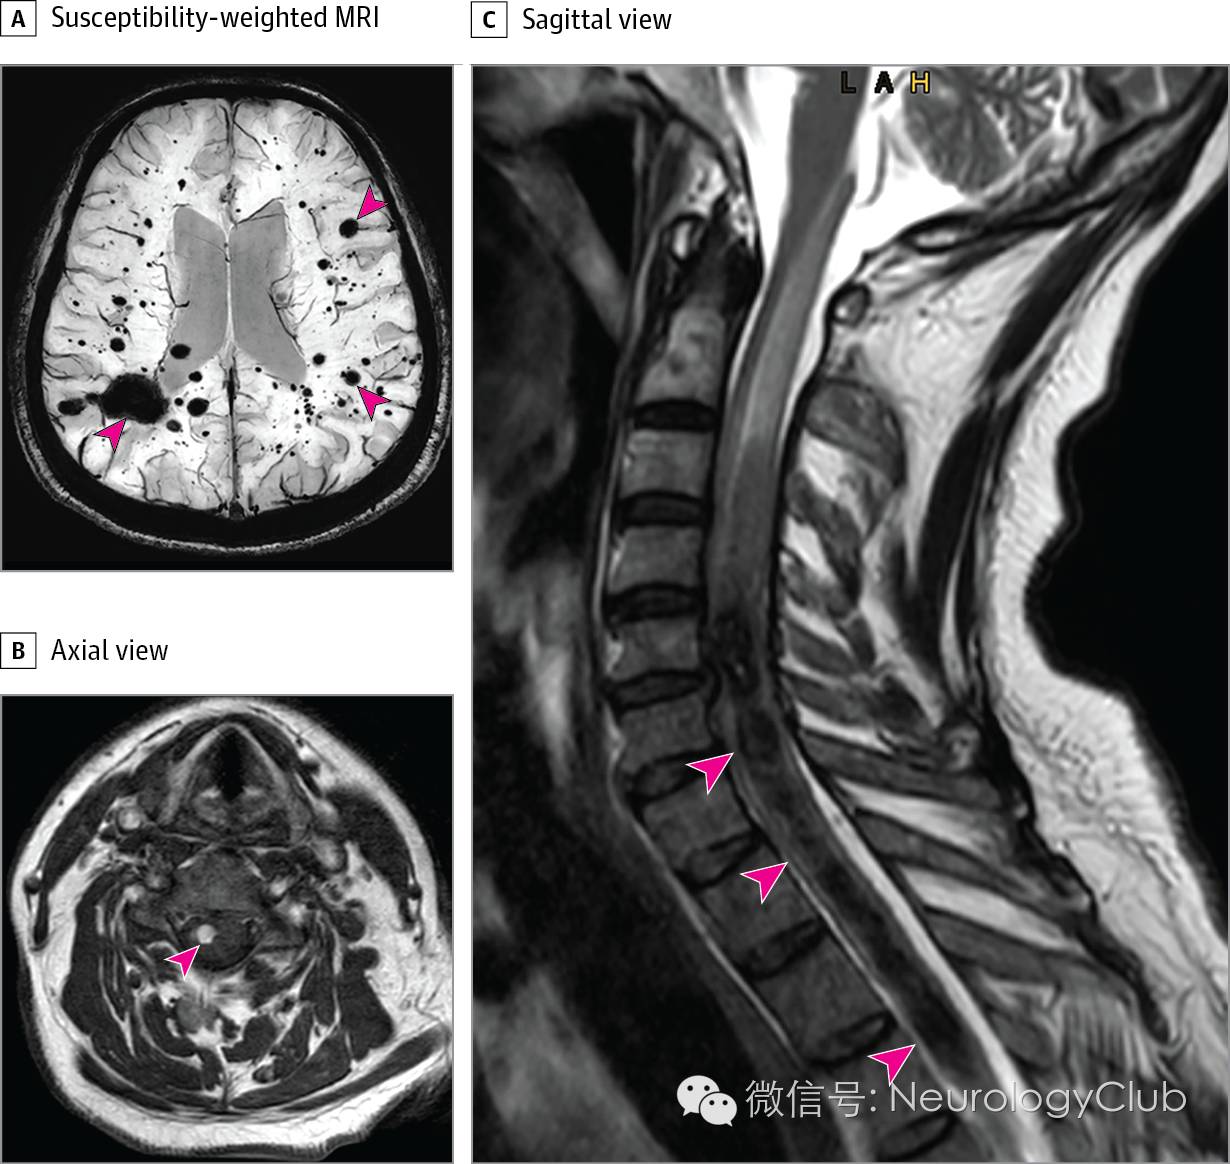

(图:A:SWI可见较多的脑实质内低信号病灶[红箭头];B:T1WI可见第5颈椎水平脊髓右腹侧高信号病灶[红箭头];C:T2WI可见C5-T7椎体水平脊髓中央低信号[红箭头])

头颅和脊髓MRI可见SWI低信号,提示多发出血。T1WI和T2WI可见不同时期的出血(未放图)以及脊髓1处急性出血(图)。

颈髓右腹侧T1高信号符合急性出血,与患者症状一致。其下方可见较大的脊髓空洞,T2WI上为低信号,符合血性空洞(hematosyrinx)改变,这是髓内肿块的罕见并发症。患者的临床表现符合Brown-Sequard综合征。